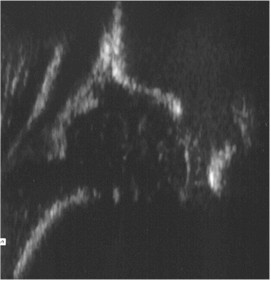

Przedstawiony ultrasonogram stawu biodrowego noworodka przedstawia następujący typ rozwojowy wg klasyfikacji Grafa:

Pytanie 101